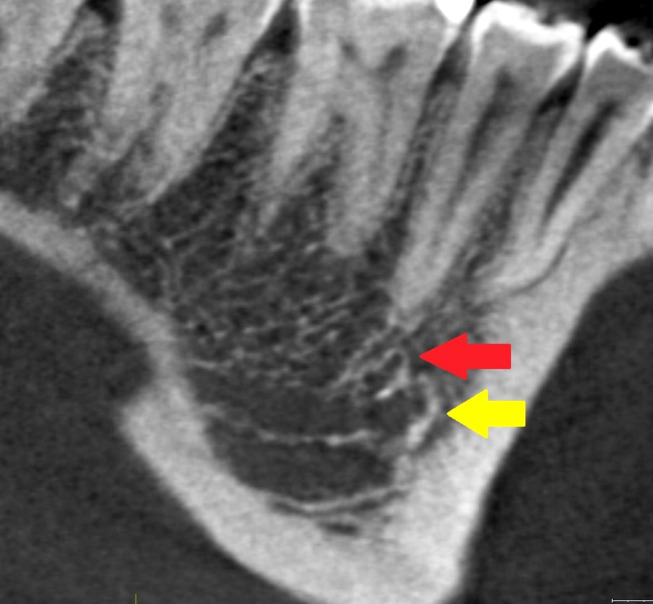

背景/目的:下颌骨管(MC)的解剖已经在文献中被广泛描述。许多研究对其解剖变异和异常进行了研究。多年来,人们使用了不同的方法来研究下颌骨,并提出了不同的分类方法。患者和方法:进行文献检索,以确定有关下颌管,双裂和三裂下颌管的文章。这项搜索使用了PUBMED和WoS计算机数据库,时间从1931年到2023年。不属于检索范围的研究被排除在外,例如那些摘要为初步评价提供的信息不足的研究。另外,一些没有被数据库检索到的文章,包括病原学方面的文章,是手工输入的。对于所有被认为符合条件的研究,检索并下载了文章全文。结果:根据文献分析,MC的变异可分为二裂MC、三裂MC、下颌内副管和牙管。下颌外颊管和舌管需要重点研究,因为它们非常频繁,数量众多,并且具有营养功能。结论:本文强调了MC变异的一些重要的放射学和解剖学方面,以及它们与实际分类的临床意义。有些分类仅具有统计和历史价值,对牙医和口腔外科医生没有实际用途。如果不能正确识别重复可能会导致围手术期并发症。需要对MC的前、中、后三个部位的不同变化进行新的研究。提出了一种更有用的分类方法。

Results: Based on the analysis of the literature, the variants of the MC should be classified as bifid MC, trifid MC, intramandibular accessory canals and dental canals. Extramandibular buccal and lingual canals require focused research, because they are very frequent, numerous, and they have nutrient functions.

Conclusion: This article highlights some important radiological and anatomic aspects regarding variations of the MC and their clinical implications in relation to their actual classification. Some classifications have only statistical and historical value without real utility for dentists and oral surgeons. The presence of duplications may cause perioperative complications if they are not correctly recognized. New studies should be conducted on the different variations of MC in its anterior, middle and posterior. A more useful classification is proposed.